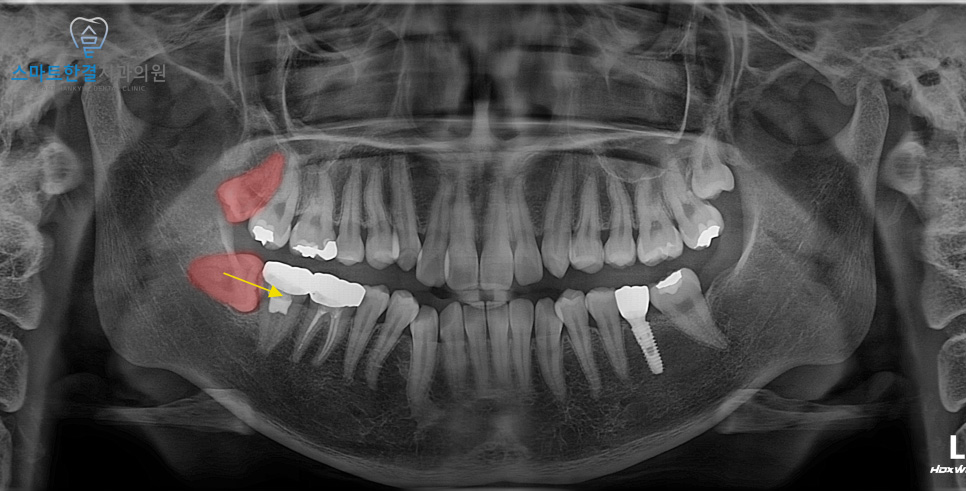

환자분께서는 아래 사랑니가 수평으로 매복된 상태로,

머리 일부만 잇몸 밖으로 노출되어 있어

잇몸 부위의 반복적인 염증과 불편감을 호소하셔서

내원해 주셨는데요.

파노라마 촬영 후 아래쪽 사랑니와

신경의 가까운 정도를 확인 위해

3D CT 촬영도 같이 촬영을 했어요.

아래쪽 사랑니는 누운 상태로 매복되어 있어

잇몸을 절개한 후 치아를 분할하여

발치하는 방식으로 진행하며

위쪽도 같이 진행하였는데요.

특히 사랑니와 밀접하게 맞닿아 있는 인접 치아는,

사진에서 보시듯 이미 치료를 받고

크라운 보철물이 씌워진 상태였어요.